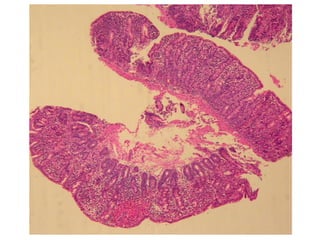

BARRETT’S ESOPHAGUS

• Defined as intestinal metaplasia of a normally SQUAMOUS

esophageal mucosa.

• The presence of GOBLET CELLS in the esophageal mucosa is

DIAGNOSTIC.

• SINGLE most common RISK FACTOR for esophageal

adenocarcinoma

• 10% of GERD patients get it

• “BREACHED” G-E junction